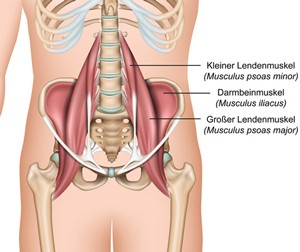

脚立の一番高い所から飛び降りたら、バランスを崩して片足で着地してしまい、腰に痛みが走りました。

病院でレントゲン撮影しても特に異常はなく、でも数日たってもお尻の方に痛みがのこり、こちらで相談したところ、仙腸関節のズレの疑いがあるといわれ、